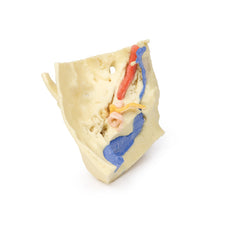

This 3D model is a midsagittal hemisection through a whole brain, preserving the right side anatomy and deep brain

structures and spaces visible in the midline. In lateral view, the right cerebral and cerebellar hemispheres are

covered in the arachnoid mater. In the midline view, the brain regions from the cerebrum to the medulla oblongata

are preserved. Centrally, the third ventricle is opened, with an intact septum pellucidum superiorly positioned and

obscuring the lateral ventricles within the cerebral hemisphere. On the inferior margin of the third ventricle both

the right mamillary body and right optic tract can be observed, whereas posteriorly the cerebral aqueduct can be

observed extending across the midbrain between the tectum and tegmentum towards the fourth ventricle (between the

cerebellum and pons). The cerebellum is separated from the occipital lobe by a preserved portion of the tentorium

cerebelli, and in cross-section the cerebellar cortex helps form the prominent arbor vitae.

A series of arterial

branches have been false coloured to contrast their course across the preserved brain structures. In the midsagittal

view the anterior cerebral artery courses from around the corpus callosum to supply the cingulate gyrus and other

midline cortical regions. The base of the middle cerebral artery can be seen passing deep between the temporal and

frontal lobes, with the posterior communicating artery connecting it to a small remnant of the posterior cerebral

artery. Adjacent to the posterior cerebral is the superior cerebellar artery, extending laterally to pass between

the temporal lobe and the cerebellum before passing deep into the transverse fissure.